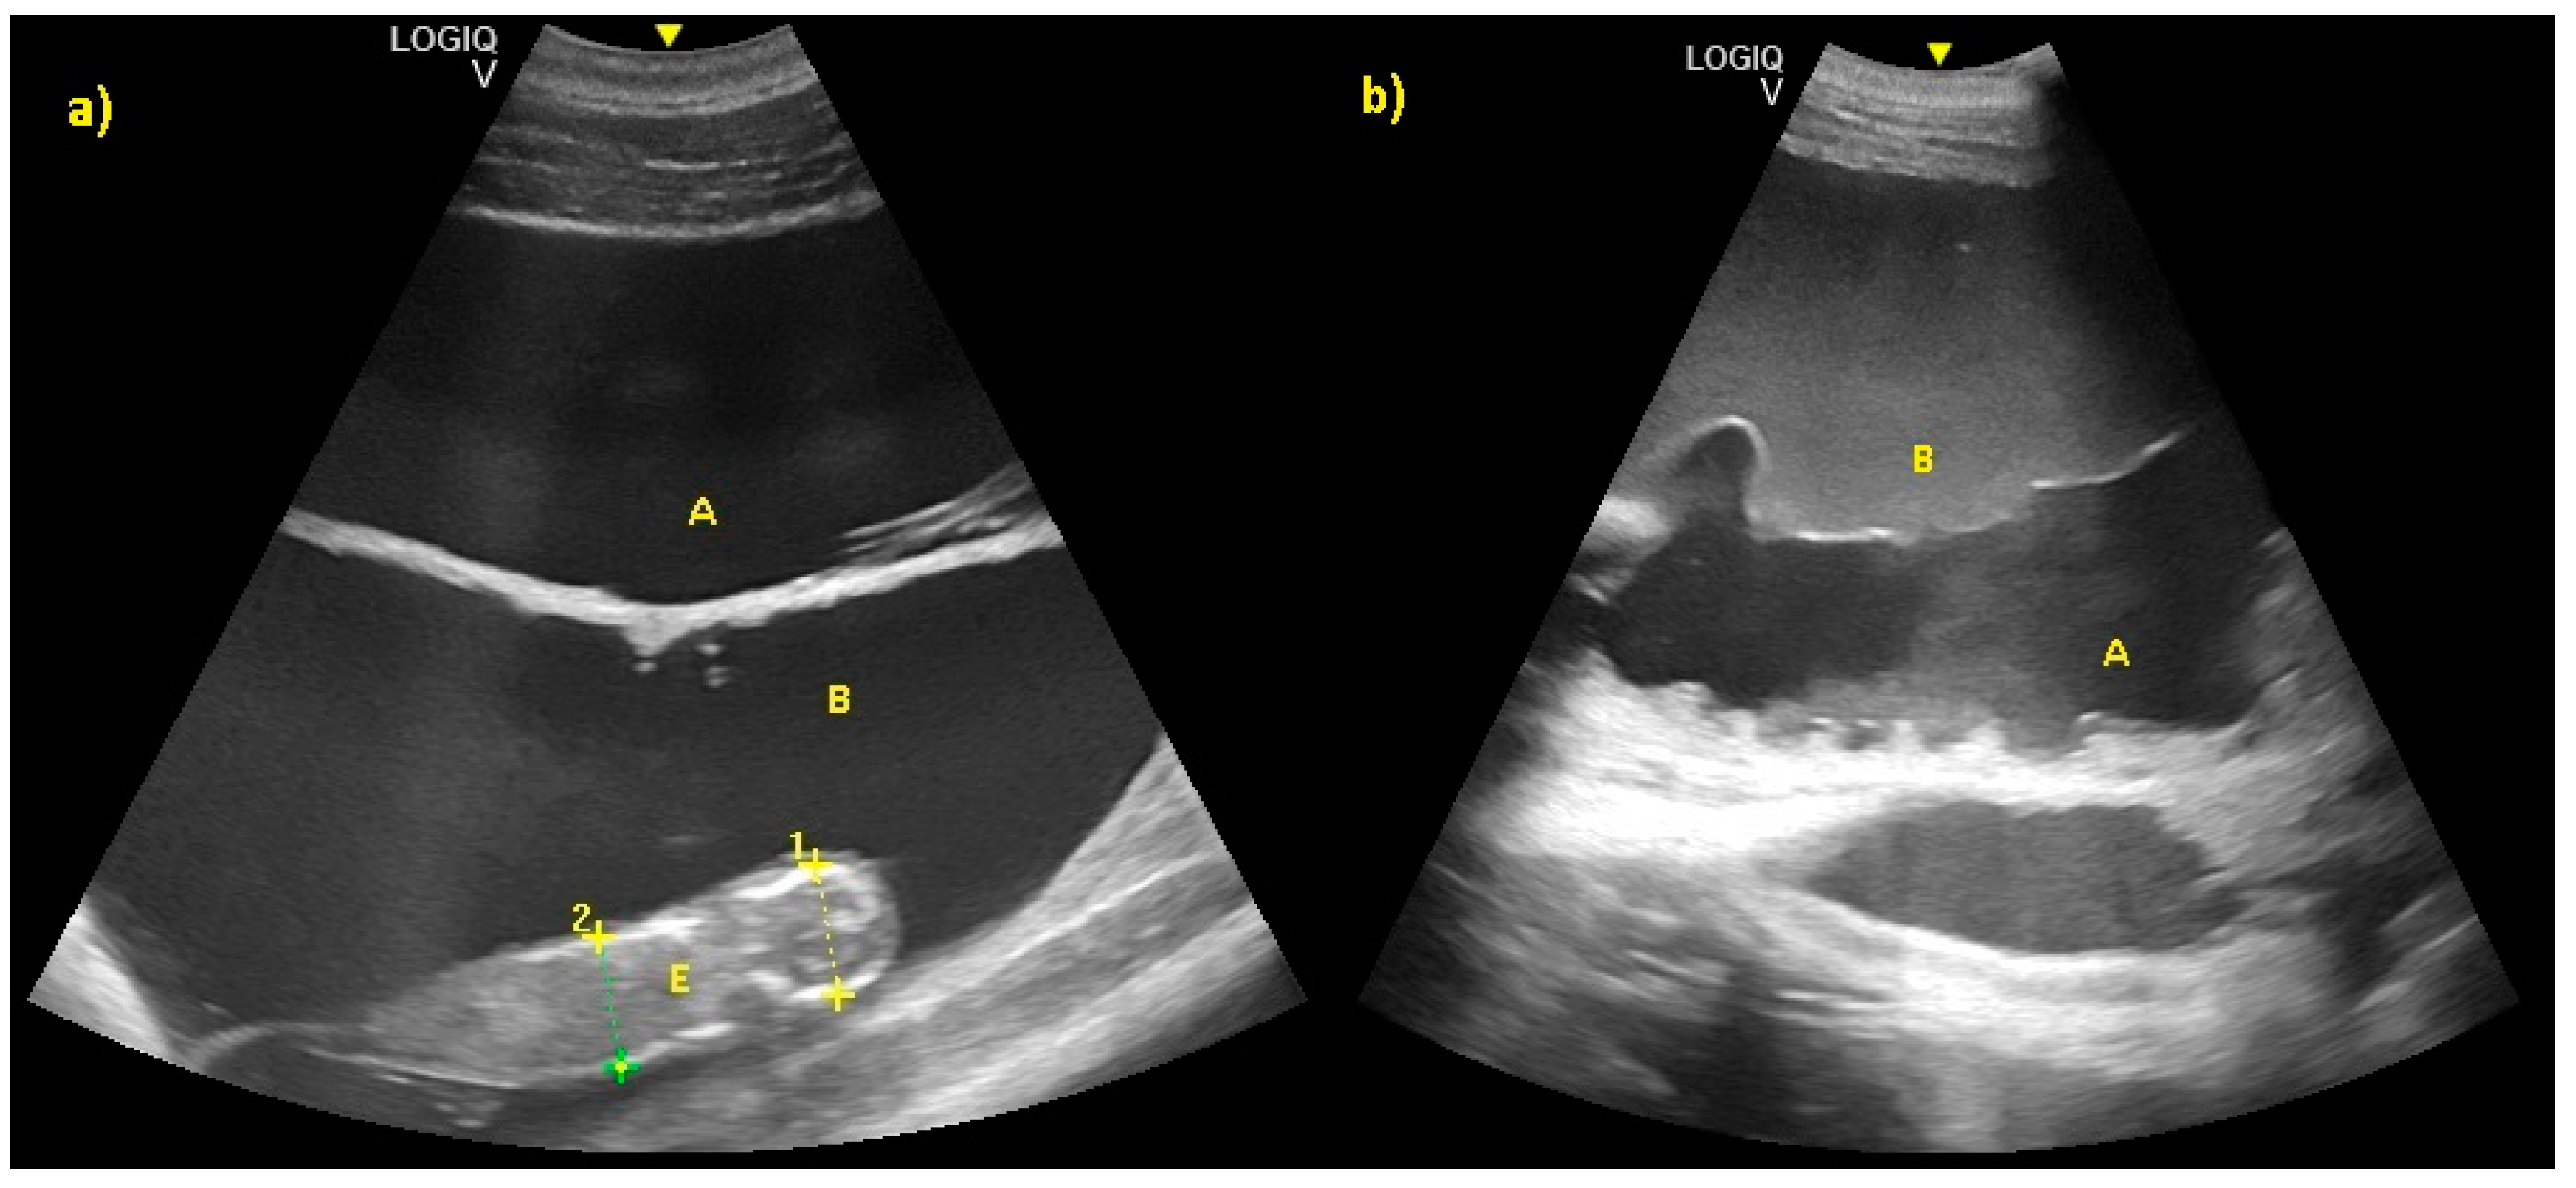

Pregnancy and Fetal Development: Cephalic Presentation and Other Descriptive Ultrasonographic Findings from Clinically Healthy Bottlenose Dolphins (Tursiops truncatus) under Human Care

3. Results